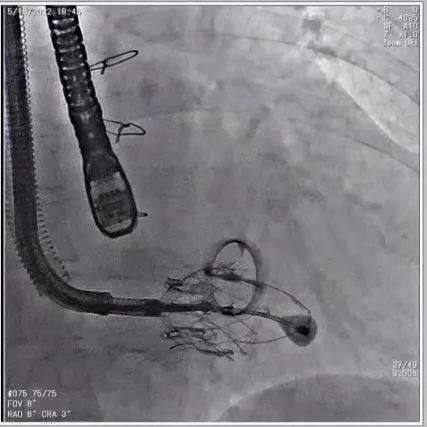

根据术前评估结果,郭应强教授团队为患者量身定制了手术策略,决定使用LuX-Valve Plus经血管三尖瓣置换系统开展手术治疗。手术在全麻下进行,采用经右侧颈静脉入路,在经食道超声和DSA的指引下调整输送器角度以达到正确位置,勾住前瓣后逐步释放盘片,盘片打开后顺利扎针,最终完成瓣膜植入,输送器撤出。术后超声提示人工三尖瓣同轴性良好,瓣架固定牢靠,无反流和瓣周漏,术后三尖瓣平均跨瓣压差为1 mmHg。

术后DSA造影